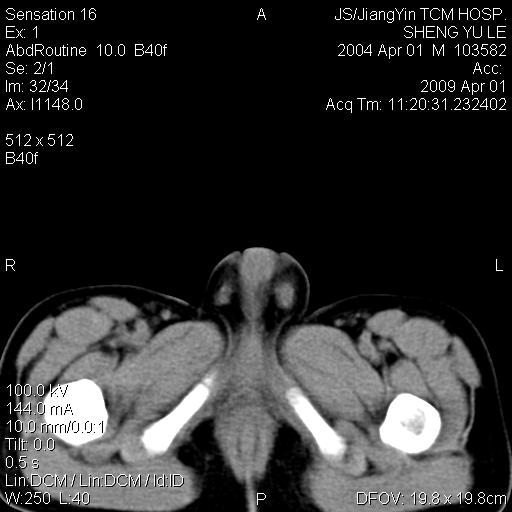

m,5岁。尿痛尿频数天。既往无病史。ct平扫腹盆腔积液。膀胱壁明显增厚。另可见心包增厚。wbc5万,骨髓穿等结果。请指教。

膀胱影像表现结合临床应该是急性膀胱炎症,但为什么有腹水呢?双肾输尿管无扩张,泌尿系压力应该不大不至于引起尿外渗,应该是腹膜感染引起的,但楼主没有提及相关症状,腹膜及膀胱结核?患者白细胞5万(结核不至于这么高啊),脾脏增大,是不是有白血病?进一步检查。。